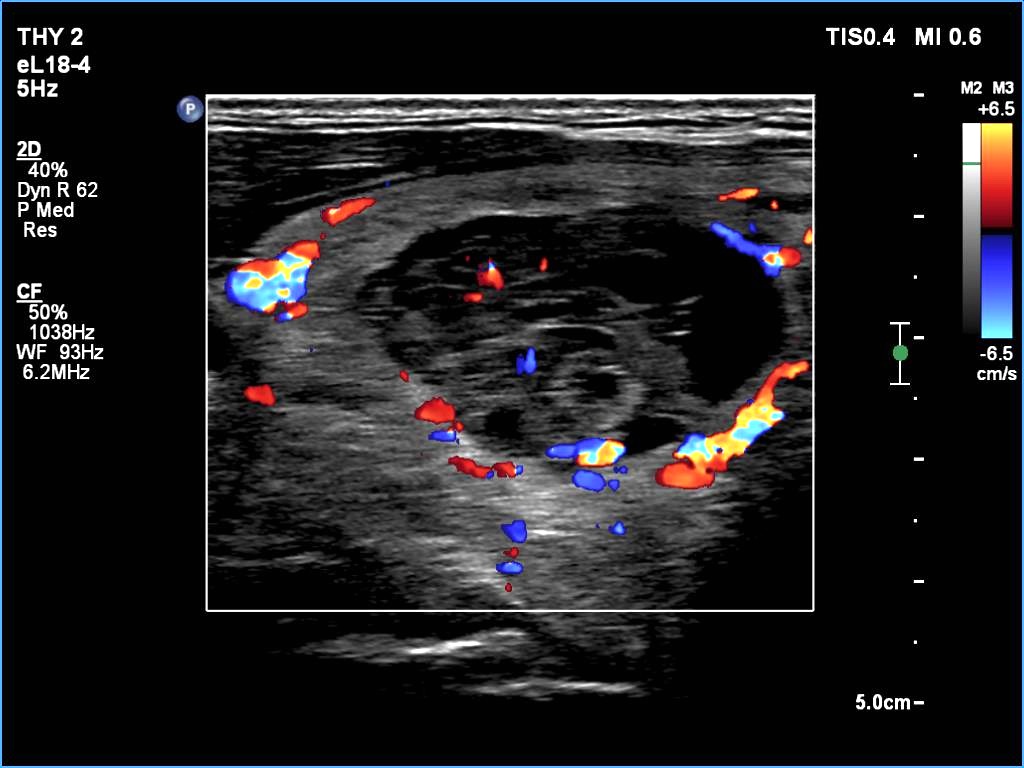

Ultrasonography: The thyroid was echonormal. There was a larger nodular mass in the right lobe which was composed of a dominantly solid echonormal portion that surrounded a dominantly cystic area. There were multiple nodules in the left lobe. The latter included an almost completely cystic lesion.

Comment. The right nodule is dominantly solid one because the cystic portion is less than 50%. The cystic portion of the nodule is multichambered which presents spongiform areas. The left cystic nodule is an almost completely cystic lesion, that has disappeared after the removal of cystic fluid.